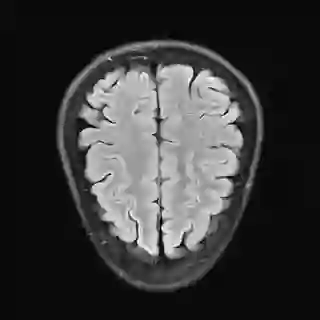

This article presents a novel undersampled magnetic resonance imaging (MRI) technique that leverages the concept of Neural Radiance Field (NeRF). With radial undersampling, the corresponding imaging problem can be reformulated into an image modeling task from sparse-view rendered data; therefore, a high dimensional MR image is obtainable from undersampled $k$-space data by taking advantage of implicit neural representation. A multi-layer perceptron, which is designed to output an image intensity from a spatial coordinate, learns the MR physics-driven rendering relation between given measurement data and desired image. Effective undersampling strategies for high-quality neural representation are investigated. The proposed method serves two benefits: (i) The learning is based fully on single undersampled $k$-space data, not a bunch of measured data and target image sets. It can be used potentially for diagnostic MR imaging, such as fetal MRI, where data acquisition is relatively rare or limited against diversity of clinical images while undersampled reconstruction is highly demanded. (ii) A reconstructed MR image is a scan-specific representation highly adaptive to the given $k$-space measurement. Numerous experiments validate the feasibility and capability of the proposed approach.